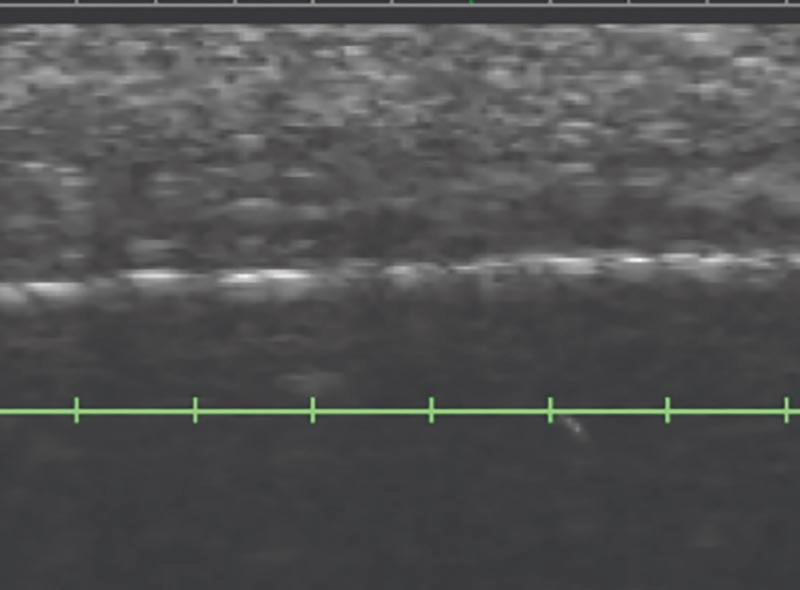

專利DeepSEETM智能超音波影像技術,判斷肌膚治療層次

透過即時影像,量身打造客製化療程

即時監測,精準傳遞音波能量,療程更安全高效